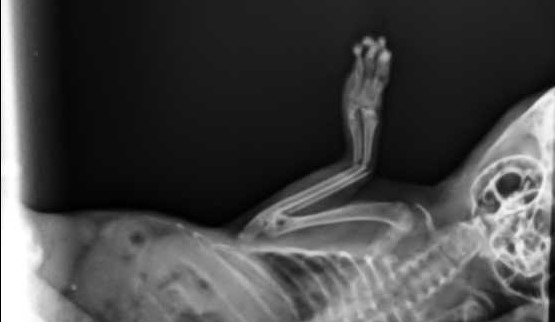

Velmi komplikovaná fraktura obou předloketních kostí u drobné činčily, jelikož se tak drobné implatáty běžně nevyrábějí, řešili jsme ji implantací nitrodřeňových hřebů vyrobených z injekčních jehel. Pacient se kompletně a bez následků uzdravil, po vyjmutí hřebů nožičku naplno používá.